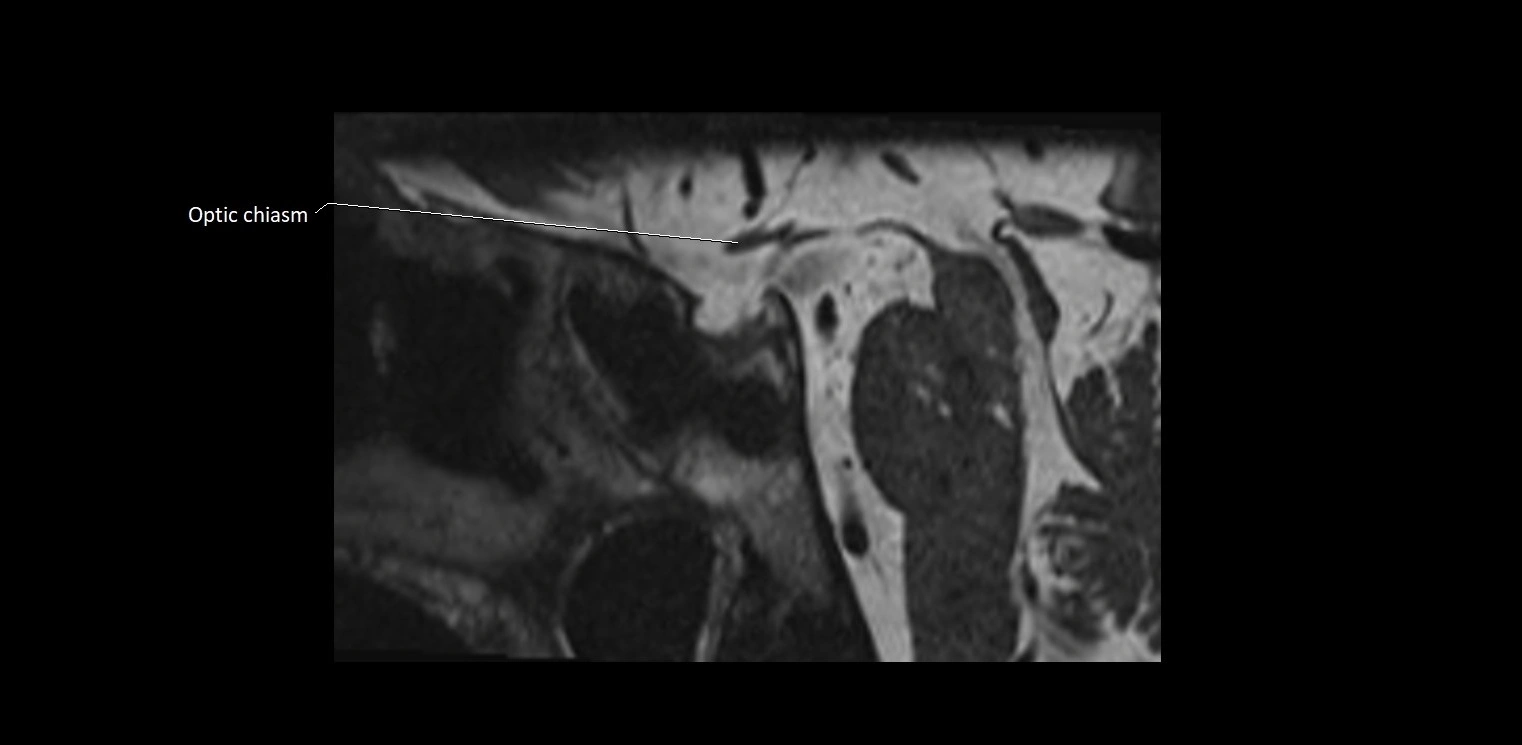

MRI images

image